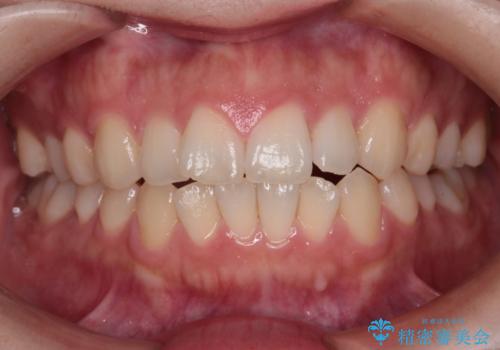

【インビザライン】前歯の凸凹を治したい

- 前歯の凸凹を主訴に来院されました。

インビザラインにて臼歯部の遠心移動を行いながら、できるだけ前歯が出ないように気を付けて治療を行っています。